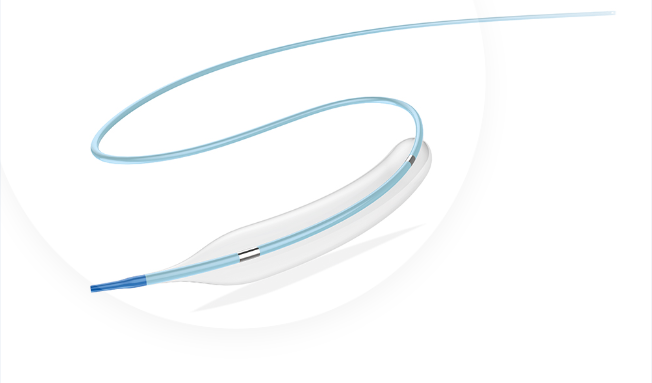

Tadpole™

Coronary Dilation Catheter

Coronary Dilation Catheter

Tadpole™ and Mini Tadpole™ models. Available in Compliant and Semi-Compliant versions.

CORONARY DILATATION CATHETER

Tadpole ™ & MiniTadpole ™

This catheter is a kind of rapid exchange catheter with an integrated shaft system and a balloon near the distal tip. The balloon has two radiopaque markers to aid in positioning the balloon in the stenosis, and is designed to provide an expandable segment of known diameter and length at a specific pressure.

0.017" SOFT TAPERED TIP

SHORT AND ROUND SHOULDER DESIGN

HYDROSURF ™ COATING ON DISTAL SHAFT

PEBAX BALLON MATERIAL

GREAT RE-FOLDING ABILITY

AVAILABLE: COMPLIANT AND SEMI-COMPLIANT